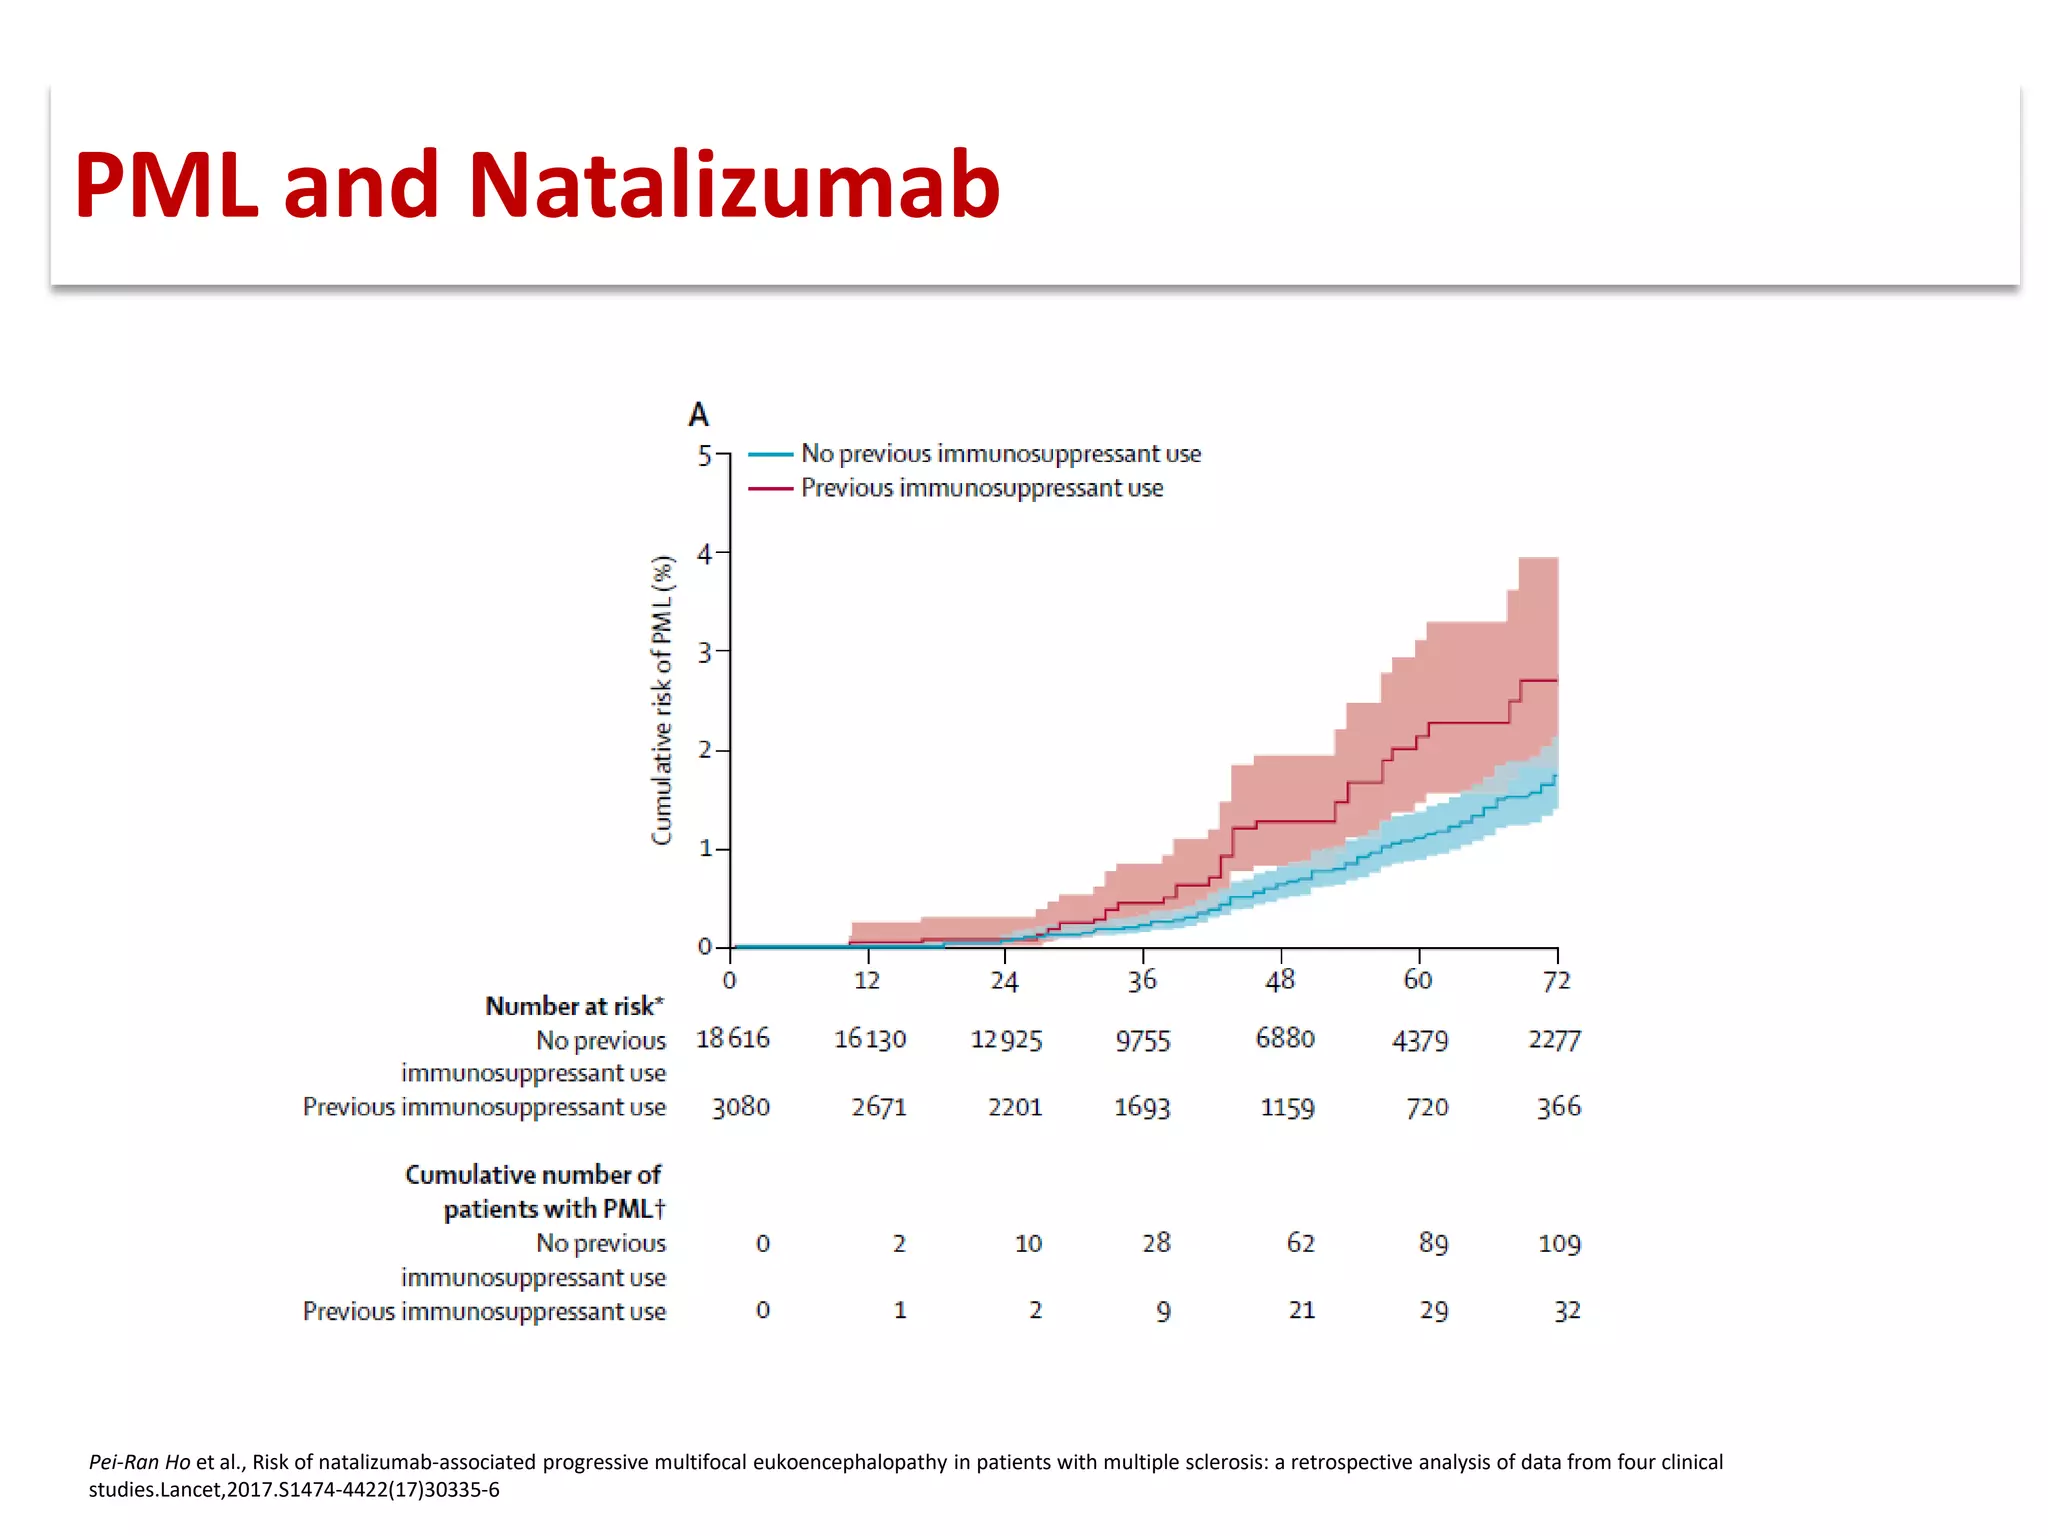

This document discusses progressive multifocal leukoencephalopathy (PML), an opportunistic infection caused by the John Cunningham virus (JCV) that leads to demyelination in the central nervous system. It highlights the epidemiology, clinical manifestations, diagnostic methods, and risk factors associated with PML, particularly in immunocompromised patients and those undergoing immunomodulatory therapies. It also presents data on the incidence of PML in patients treated with natalizumab and other therapies, addressing the relationships between these treatments and the development of PML.